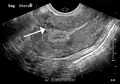

Diagnosis

Physical examination and ultrasound are sufficient for diagnosing uterine fibroids in the majority of patients. When ultrasound findings are inconclusive, magnetic resonance imaging (MRI) may be able to confirm the diagnosis of uterine fibroids in most cases. In addition, MRI can identify benign uterine fibroids with atypical imaging features and fibroids with variant growth patterns. MRI can also identify other uterine (e.g. adenomyosis, endometrial polyps, endometrial cancer) and extrauterine (e.g. benign and malignant ovarian tumors, endometriosis) disorders that may mimic the appearance of uterine fibroids and/or contribute to the patient's symptoms.[37] However, a small proportion of uterine fibroids can mimic other malignant uterine tumors (e.g. leiomyosarcoma) on all available imaging modalities (e.g. ultrasound, CT, MRI and PET-CT).[37]